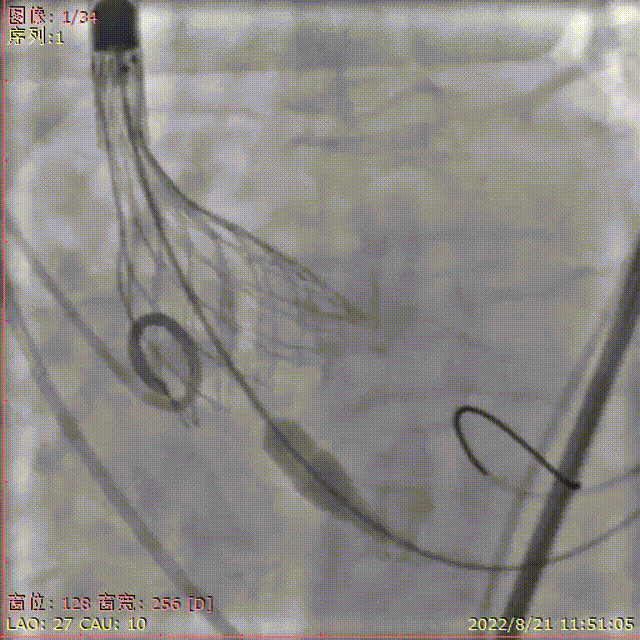

术中剪影

手术影像记录

主动脉根部造影

18mm球囊预扩

输送器顺利过弓跨瓣

瓣膜初始定位

工作位多角度评估瓣膜形态,位置理想

缓慢稳定完全释放瓣膜

球囊后扩,改善瓣膜形态

最终造影,位置理想,无瓣周漏

外周造影检查